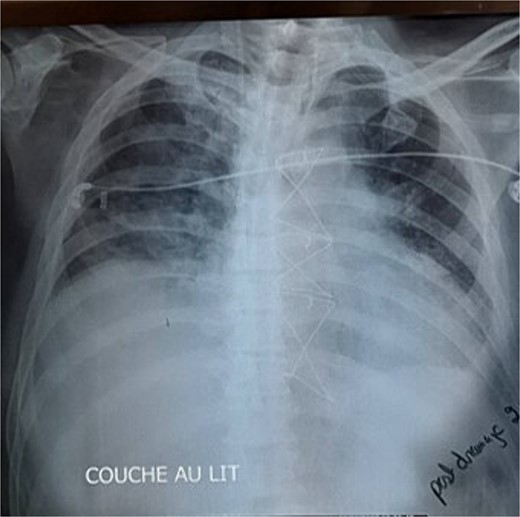

Given these findings, CABG was deemed necessary, with plans to place the left internal mammary artery (LIMA) to the LAD, right internal mammary artery (RIMA) to the RCA, and a saphenous vein graft to the first marginal. Intraoperatively, while dissecting the LIMA graft, total pericardial agenesis was unexpectedly discovered, manifesting as a collapsed parietal pleura and total leftward heart deviation. We performed uneventfully the CABG and we decided to not treat the pericardial agenesia. Postoperatively, the patient underwent extubating on the same day but developed non-sustained tachycardia on the electrocardiogram and recurrent unilateral pulmonary edema, particularly notable when he assumed a semi-upright position. The chest X-ray showed right pulmonary edema (Fig. 1), with total deviation of the heart to the left, as well as an elongation and straightening of the left heart border. The right cardiac border was also absent. The TTE showed an LVEF of 30%, high pulmonary arterial pressure = 50 mmHg. We hypothesized that this positional and unilateral pulmonary edema was related to the torsion of the heart and the elongated right pulmonary vein, caused by the deviation of the heart to the left due to the lack of pericardium.

The chest X-ray showed right pulmonary edema, with total deviation of the heart to the left, as well as an elongation and straightening of the left heart border.

A variety of imaging modalities can be helpful for the evaluation and diagnosis of congenital absence of the pericardium. Typical chest X-ray findings, particularly for a left complete pericardial defect, include loss of the right heart border, a leftward shift and straightening of the left cardiac border (Snoopy sign), and lung tissue between the left hemidiaphragm and the base of the heart as well as between the aortic knob and main pulmonary artery [8].